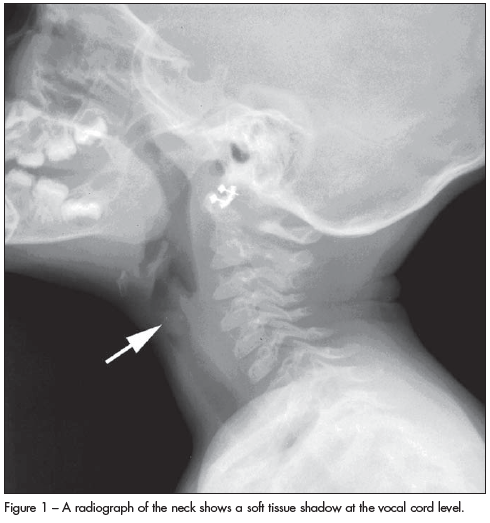

Juvenile laryngeal papillomatosis is usually characterized by wart-like exophytic lesions that have a predilection for the larynx.